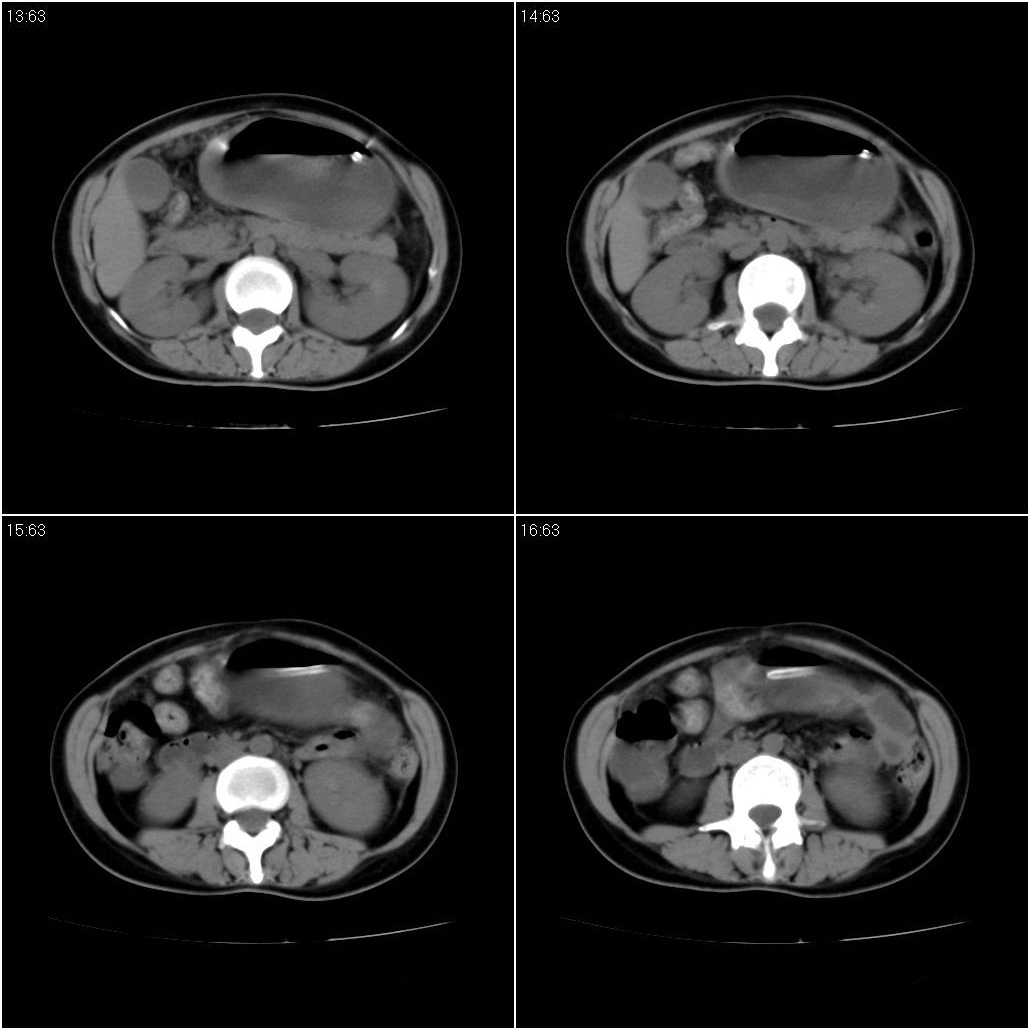

女性,33岁。4个月前因妊娠发现盆腔肿物。ca-125: 1100

胃幽门部癌伴小弯侧和腹腔淋巴结转移,胃内有胃管。

胃癌,梗阻情况要结合临床,无呕吐病史?

支持;胃癌【浸润】幽门梗阻.胰头、胆囊及肝左叶受侵,副脾.

考虑胃窦占位并肝门部淋巴结转移

考虑胃窦部胃癌伴小弯侧和腹腔淋巴结转移。

胃幽门部癌伴小弯侧和腹腔淋巴结转移,胃内有胃管